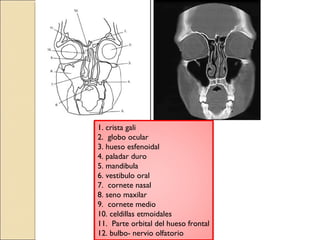

1. crista gali

2. globo ocular

3. hueso esfenoidal

4. paladar duro

5. mandibula

6. vestibulo oral

7. cornete nasal

8. seno maxilar

9. cornete medio

10. celdillas etmoidales

11. Parte orbital del hueso frontal

12. bulbo- nervio olfatorio